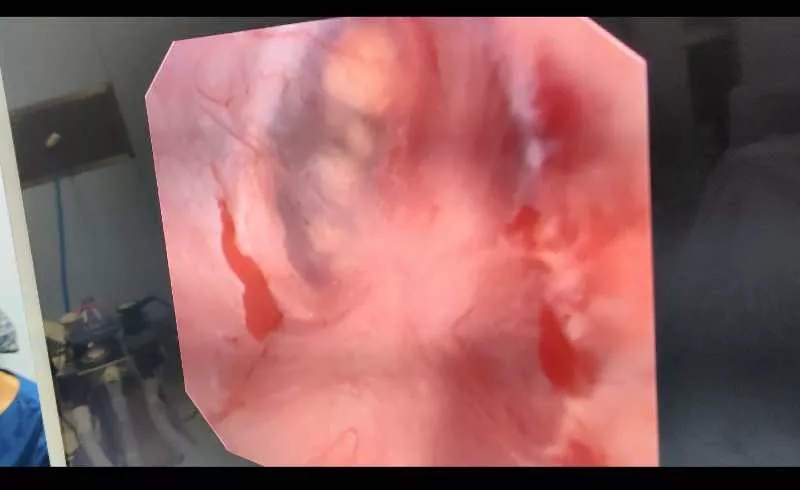

行经尿道一次性输尿管软镜钬激光碎石手术,软镜进入右侧肾盂、肾盏内发现结石图像:结石由一层薄的黏膜包裹,故患者在体外冲击波碎石后症状仍不缓解,

赵立明主任使用钬激光将包裹在结石外的黏膜打开后,进行长脉宽粉末化碎石,术后患者病人安返病房。

进行最后粉末化处理